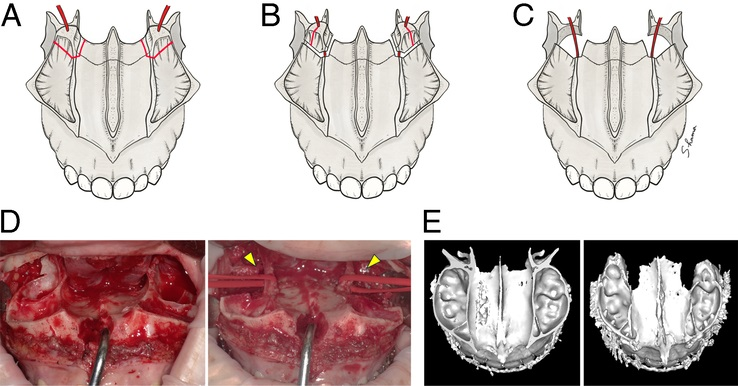

3. USO (U shaped Osteotomy)

- Bone cut shaped like a "U" around the piriform rim that mobilizes the anterior maxillary wall and ANS as one segment. The segment is advanced, rotated, and fixed with small screws.

- Projects the ANS and paranasal rims forward.

- Why vs graft/implant: Uses actual bone for a cleaner contour. Likely superior to both implants and especially grafts if done right.

- USO is a "rare" osteotomy. There are few confirmed cases online, and fewer doctors who publicly say they perform it.